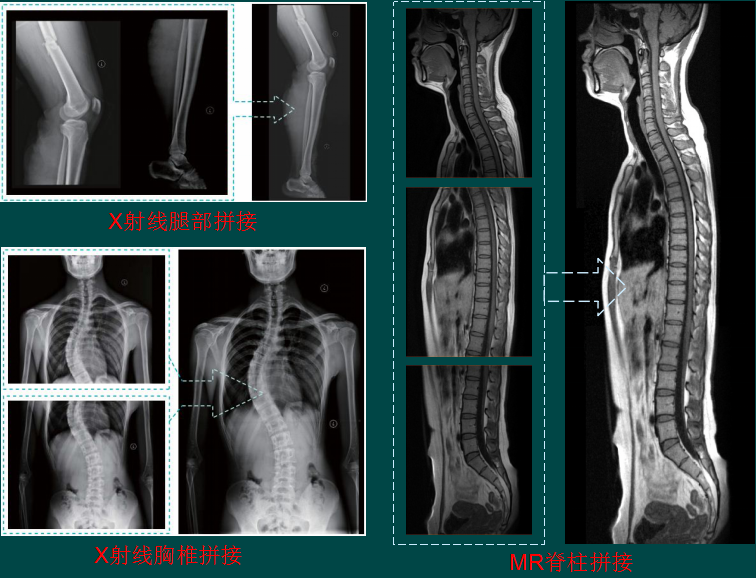

图像拼接(背景)

图像拼接是将数张有重叠部分的图像(可能是不同时间、不同视角或者不同传感器获得的)拼成一幅大型的无缝高分辨路图像的技术。

图像拼接(结果)